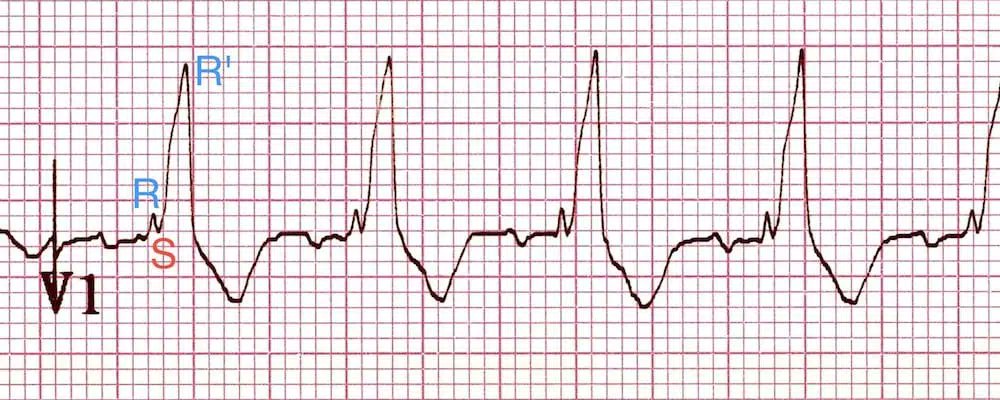

- 3rd phase: Delayed RV depolarization produces a third phase of ventricular stimulation. V1 (right-sided chest leads) records this phase of ventricular stimulation as a (+) wide deflection (R' wave).

- Will see a wide negative S-wave deflection in left-sided chest leads

- Complete: QRS > 0.12 seconds in duration w/ rSR' in lead V1 and qRS in V6

- Incomplete: Same QRS patterns, but duration is between 0.10 - 0.12 seconds